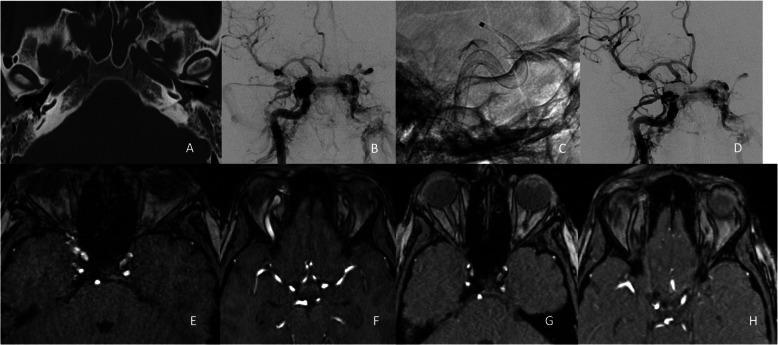

Abstract Image